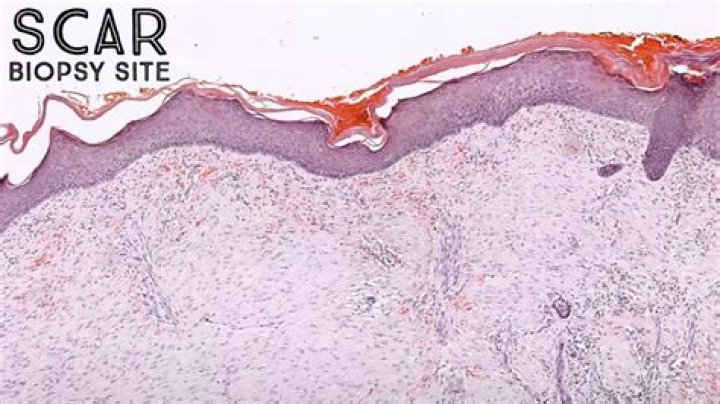

Dermatopathology is a joint subspecialty of dermatology and pathology or surgical pathology that focuses on the study of cutaneous diseases at a microscopic and molecular level. It also encompasses analyses of the potential causes of skin diseases at a basic level.

Normal Skin Histology - Explained by a Dermatopathologist